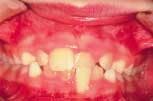

• Posterior crossbite requires early correction to increase arch length and lessen the possibility of impacted canines or future crowding, and decreases cheek-biting episodes. (Figure 2)